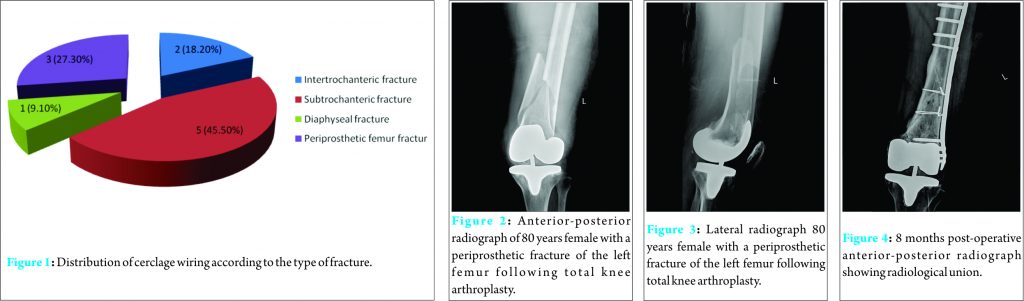

The numbers and percentages of patients with a type of fracture are shown in Fig. 1. The details of each case are given in Table 1. The mean total number of wires used was 2.10 ± 0.70.

Case Report: This is a retrospective case series of patients (January 2011 to October 2015) in whom cerclage wiring was used as an adjunct to osteosynthesis of primary and periprosthetic fractures of femur. Patient demographics, number of wires used, implant used for osteosynthesis, number of days to union, union rate and complications were recorded and analyzed. The patients were followed up for a minimum of 6 months. 11 patients (7 female and 4 male) with a mean age of 67.10 ± 21.64 years were studied. The number of patients with intertrochanteric, subtrochanteric, diaphyseal, and periprosthetic fractures of the femur was two, five, one, and three, respectively. Internal fixation was done with plates in six and cephalomedullary nails in five patients. Mean total number of wires used was 2.10 ± 0.70. Mean duration of follow-up was 15.91 ± 10.03 months. Union was achieved in all cases with a mean duration of 86.63 ± 22.44 days. There were no complications in our study.